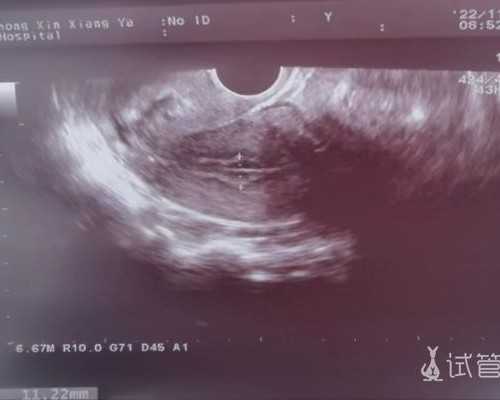

- 6周要求:满6周,且见到心管搏动,就能进行测试。

- 7周要求:孕妇的胚芽 (CRL) 需达到9mm以上或孕囊 (GS) 需达到35mm,且见到心管搏动,才可进行测试。

还有无论是6周还是7周,都要满足一年内没生过男孩、半年内没有流过男孩,以及没有进行输血、重大器官移植手术,如果满足的话才可以来进行抽血检测。准确率达99.8%。